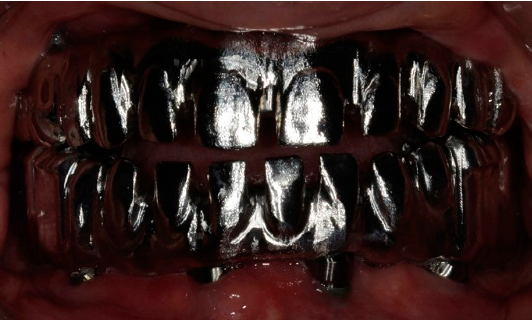

Con el fresado de las prótesis se logró un mejor ajuste pasivo en las conexiones y se evitó la formación de las burbujas que ocasiona el colado, así como la contracción que deriva en falta de ajuste pasivo. Cuando la paciente sonríe, se observa que las caras oclusales metálicas son imperceptibles (Figura 4). Con las caras oclusales metálicas se pretende mantener la dimensión vertical a largo plazo y reducir la delaminación de la porcelana.

Entre las desventajas de este tratamiento está el que las caras oclusales metálicas posteriores podrían comprometer la estética. Aun así, en nuestro caso clínico, cuando la paciente sonríe las caras oclusales metálicas son imperceptibles. De igual modo, si se colocaran caras oclusales metálicas sólo en los molares, podría haber delaminación de la porcelana en los premolares por la carga oclusal, lo cual se evitaría colocando caras oclusales metálicas en los premolares. En el caso que presentamos, la paciente optó sólo por la colocación de caras oclusales metálicas en los molares. En tercer lugar, si la estructura se hiciera con la técnica de fundición, es necesario un buen manejo de vaciado, tal como lo plantean Han et al.26. De acuerdo con AlBader et al.20, la mayor o menor dificultad del ajuste de la oclusión depende de la planeación.